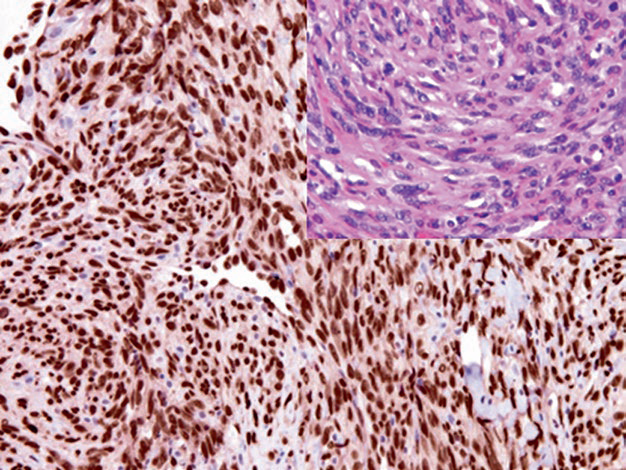

HHV-8 is a DNA virus and is the causative agent of Kaposi sarcoma, primary effusion lymphoma, and multicentric Castleman disease. Detection of latent nuclear antigen is one of the diagnostic markers for Kaposi sarcoma.

图片

Figure 4. Expression of HHV-8 latent nuclear antigen in Kaposi sarcoma tumor cells.